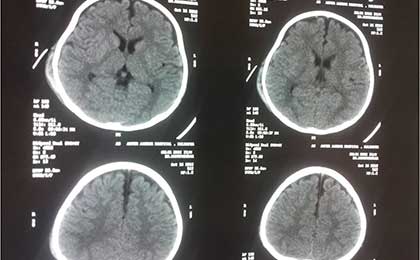

CT of Dai

• CT of Dai